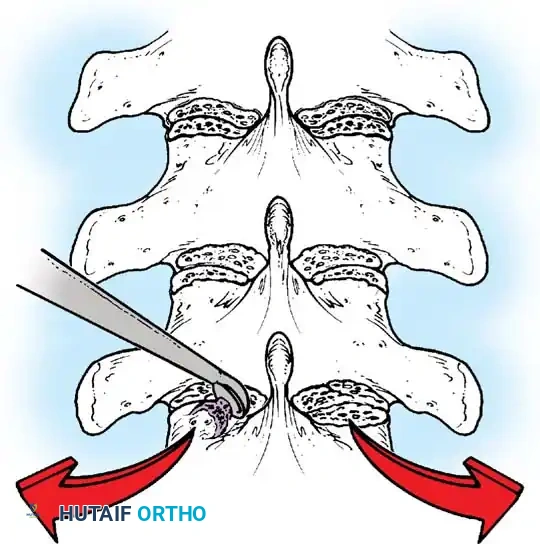

The Moe Technique (Lumbar Spine)

In the lumbar spine, the facet joints are oriented in a more sagittal plane, necessitating a modified approach.

Fig. 38-27: The Moe technique adapted for lumbar facet fusion, addressing the sagittal orientation of the joints.

- Utilize a small osteotome or a needle-nose rongeur to resect the adjoining joint surfaces.

- This creates a distinct rectangular defect within the sagittally oriented joint space.

- Pack this defect forcefully with cancellous bone graft.

- Proceed to decorticate the entire exposed posterior elements (laminae and transverse processes) using Cobb gouges, always directing force away from the spinal canal.